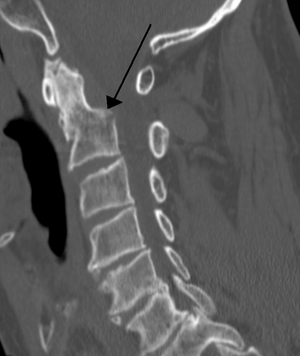

Severe pain will usually be present at the point of injury. Pressure on a nerve may also cause pain from the neck down the shoulders and/or arms. Bruising and swelling may be present at the back of the neck. A neurological exam will be performed to assess for spinal cord injury. X-rays will be ordered to determine the severity and location of the fracture. CT (computed tomography) scans may be ordered to assess for gross abnormalities not visible by regular X-ray. MRI (magnetic resonance imaging) tests may be ordered to provide high resolution images of soft tissue and determine whether there has been damage to the spinal cord, although such damage is usually obvious in the conscious patient because of the immediate functional consequences of numbness and paralysis in much of the body.

It is also common for imaging (either a plain film X-ray or CT scan) to be completed when assessing a cervical injury. This is the most common way to diagnose the location and severity of the fracture. To decrease the use C-spine scans yielding negative findings for fracture, thus unnecessarily exposing people to radiation and increase time in the hospital and cost of the visit, multiple clinical decision support rules have been developed to help clinicians weigh the option to scan a patient with a neck injury. Among these are the Canadian C-spine rule[1] and the NEXUS criteria for C-Spine imaging,[2] which both help make these decisions from easily obtained information. Both rules are widely used in emergency departments and by paramedics.